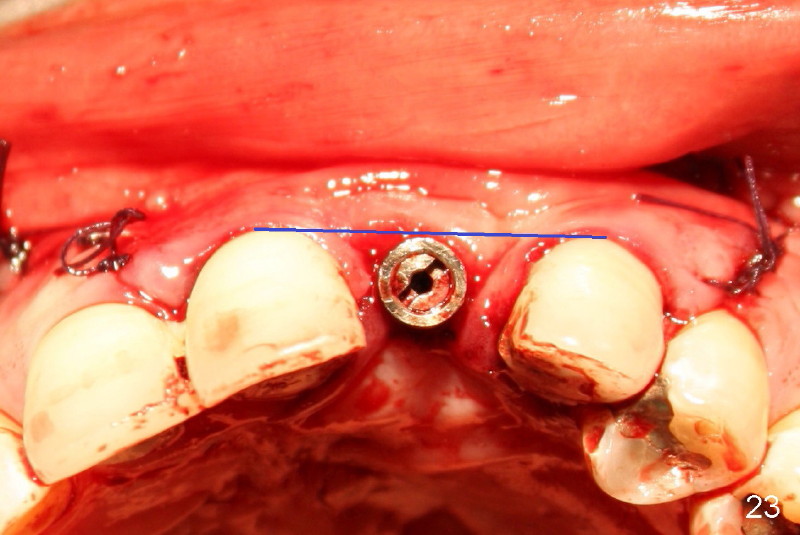

Segmental Osteotomy for Misplaced Implant

This corrective surgery was performed by Dr. Bernee Dunson.

Xin Wei, DDS, PhD, MS 1st edition 12/21/2011, last revision 12/23/2011